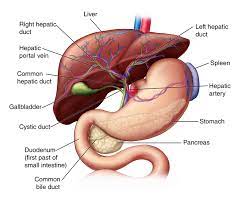

LIVER:

The liver is the most important organ of the metabolic system. It helps convert nutrients into usable substances, detoxifies certain substances, and filters blood coming from the digestive tract through a vein before it joins venous blood flow from other parts of the body. Oxygenated blood reaches the liver via an artery.

The majority of liver mass is in the upper right side of the abdomen, just under the rib cage.

The liver plays many roles in digestion and filtering the blood, including:

producing bile

helping the body filter out toxic substances, including alcohol, drugs, and harmful metabolites

regulating blood levels of various important chemicals, including amino acids

making cholesterol

removing some bacteria from the blood

making some immune factors

clearing bilirubin from the blood

regulating the process of blood clotting, so that a person does not bleed too much and does not develop dangerous blood clotsThe liver partners with the gallbladder to deliver bile to the small intestine. The liver pours bile into the gallbladder, which then stores and later releases the bile when the body needs it to help with digestion.